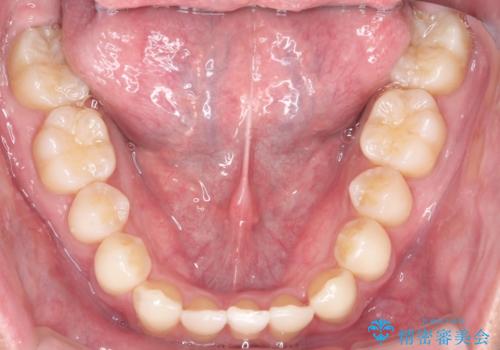

- 前歯のがたつきが気になるとのことで来院されました。

骨格的なところと、上下の歯の大きさのことを考慮して、下の前歯を1本抜歯し、インビザラインにて矯正治療することとなりました。

上の前から2番目の歯がもともと小さかったため、最後にかぶせ物を装着することで、自然な仕上がりにできました。